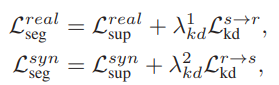

그리고 위의 직접 학습과 간접 학습을 결합하여 S_{real}과 S_{syn}를 학습시키는 LOSS는 아래 식과 같습니다.

그리하여 이를 최종적으로 합한 loss는 아래와 같고 한꺼번에 학습이 진행됩니다.